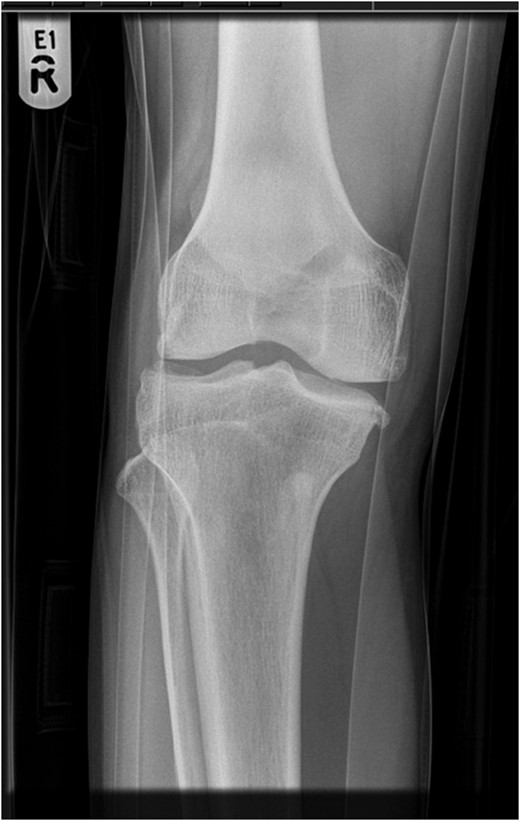

A 30-year-old gentleman woke up with a sudden onset of knee pain. He had never experienced any knee problems in past. The emergency department referred him as a suspected patellar tendon rupture. History, examination and radiographs revealed a characteristic superior patellar dislocation. No obvious generalized ligament laxity, genu recurvatum or patella alta was found. Hydrodilatation of his knee was performed using 10 ml of 0.5% Chirocaine diluted in 20 ml of 0.9% normal saline. Dislocation was reduced successfully with gentle digital manipulation. Full pain free range of motion was demonstrated after reduction. He was discharged home the same day with no recurrence at 6 months.

A thorough history and careful examination is essential for diagnosis. Due to its rarity, the emergency department usually refer this condition as patellar tendon rupture. It is easy to diagnose if clinician is aware and vigilant. Patient will not be able to do a straight leg raise in both conditions, but for different reasons. It is due to pain in superior patellar dislocation, while loss of extensor mechanism continuity is the cause in patellar tendon rupture. Most cases involved trivial or no trauma in superior patellar dislocation, with contraction of quadriceps in extended knee. Superior movement of the patella locks its lower articular margin on upper border of trochlea. The less frequent mechanism is direct impact on patella. In contrast, rupture of patellar tendon requires significant force and often is a consequence of eccentric contraction of quadriceps.

Knee cannot be flexed actively or passively in superior patellar dislocation, which is the most important differentiating point. Patients with patellar tendon rupture generally have less pain, knee can be passively flexed and often a gap is palpable in patellar tendon area. It should not be forgotten that a tense hematoma in tendon gap is possible.